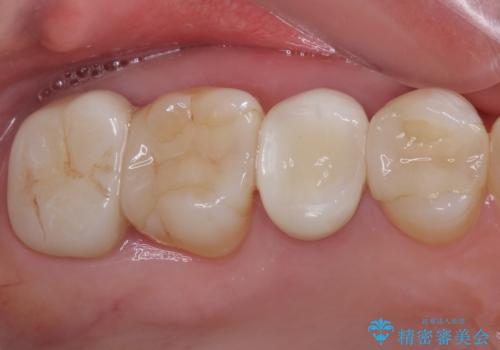

右上の歯は、第二小臼歯の初回処置後に痛みを感じなくなったため、他の歯については問題なしと診断しました。

将来ホワイトニングをされるとのことで、前歯よりもやや白い色合いのオールセラミッククラウンを選択されました。